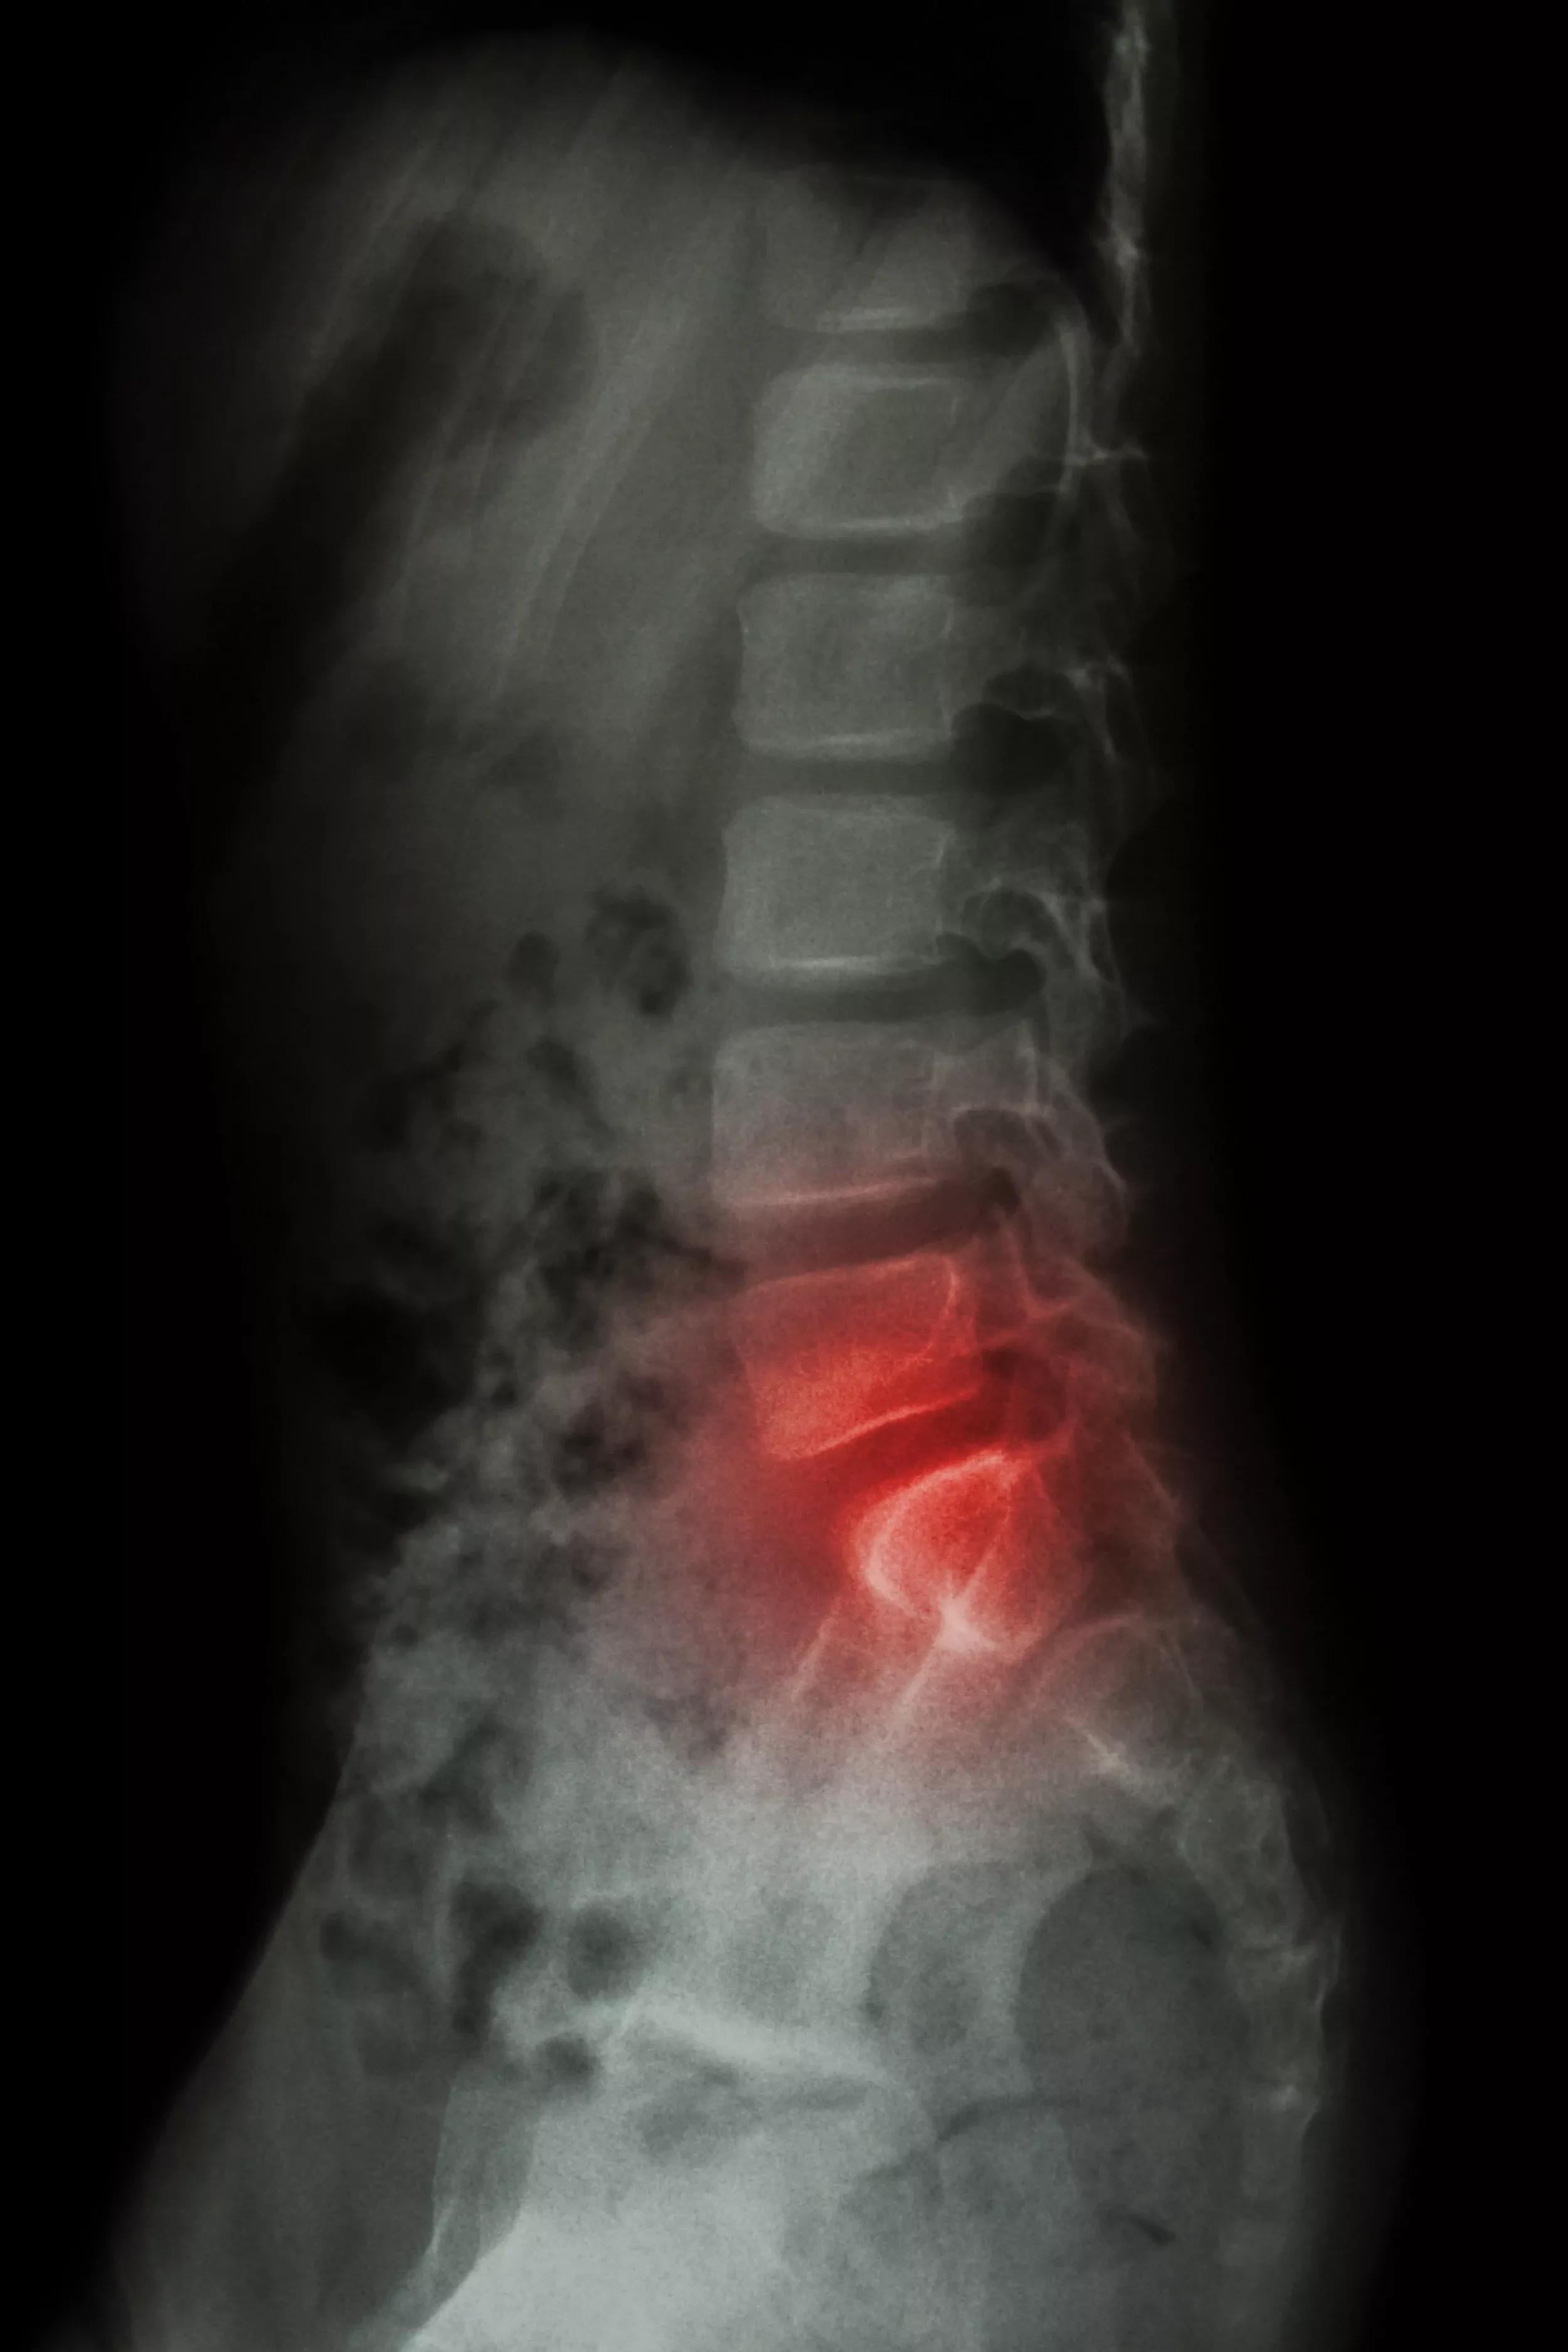

✔ Arthritis in the Hips or Spine:

When your hips or low back are injured or aren't functioning properly, your body does it's best to adapt to the situation so that you can keep moving. In the beginning this adaptation takes the form of muscles compensating for the issue. Over time the muscles can become weak and can no longer handle adapting to the stress on the body.

When muscle adaptation starts to fail, your body makes a more permanent adaptation to the stress that is being put on it. To do this, your body will start to change the structure of the skeleton in order to help. This is part of what causes the process of

degenerative arthritis in your body. While this "adaptation" helps your body deal with the stress that is being put on it, it also causes some very permanent issues that will eventually turn into chronic low back issues.